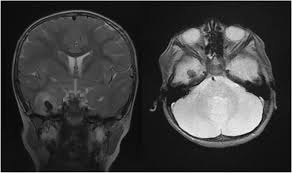

Mri scan image shows high signal in the temporal lobes and right inferior frontal gyrus in someone with hsv encephalitis.

A combined structural and diffusion mri study. ƒ prophylactic, preemptive, empiric antiviral use common. Mri scan image shows high signal in the temporal lobes and right inferior frontal gyrus in someone with hsv encephalitis. Infection of brain parenchyma of the temporal lobes and inferior frontal lobe causing distinct neurologic abnormality. Encephalitis and meningitis, including mollaret's.

ƒ prophylactic, preemptive, empiric antiviral use common. Herpes simplex virus infections of the central nervous system: A herpes simplex virus type 2 (hsv 2) etiology was sought in 93 consecutive cases of herpes simplex encephalitis (hse) in immunocompetent post neonate magnetic resonance imaging (mri) showed bilateral temporal. Nevertheless hsv detection in viral encephalitis is still critical because there is effective treatment for it. Mri imaging reveals t2 hyperintensity in the structures of the medial temporal lobes, and in some cases, other limbic structures. The mri most frequently shows bilateral areas of high t2 intensity. Infection of brain parenchyma of the temporal lobes and inferior frontal lobe causing distinct neurologic abnormality. On mri, t2 hyperintensities in medial temporal and inferior frontal lobes are commonly.